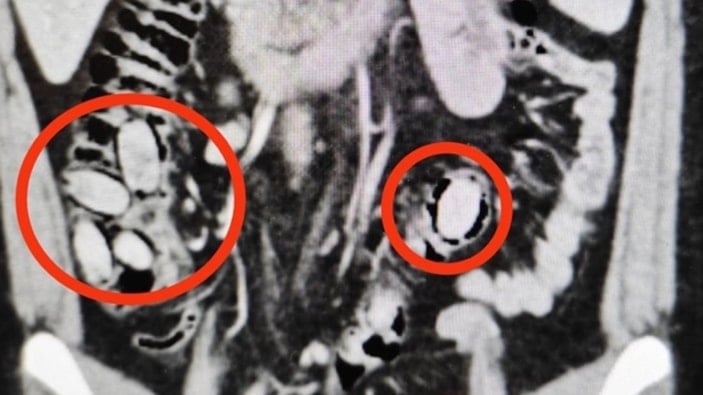

Hastane kontrolüne götürülen 25 yaşındaki S.A.'nın midesinde 44 kapsül sentetik uyuşturucu olduğu belirlendi.

Operasyonla midesindeki kapsüller çıkarılan S.A., hastanedeki tedavisinin ardından sevk edildiği adliyede çıkarıldığı hakimlikçe tutuklandı.